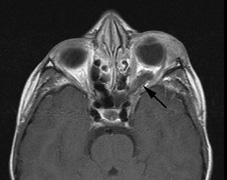

1. Schwannomas most commonly affect the fifth cranial nerve (CN), but any cranial nerve may be affected. In contrast to vestibular schwannomas (CN VIII), these typically do not grow large.84,90 Vestibular schwannomas (acoustic neuromas) are the classic finding in NF2 (Fig. 7). The risk for malignant transformation is low, but may be higher with radiation exposure.84,94

Fig. 7. Neurofibromatosis type 2: Images of a 12-year-old boy with deafness and weakness in his arms and legs, whose father has bilateral deafness. Axial T2-weighted (a) and postcontrast axial (b) T2-weighted images reveal bilateral vestibular schwannomas, which are also known as acoustic neuromas (arrows). This is the classic finding of NF2. (b, c) Bilateral schwannomas are seen in Meckel's cave (arrowheads) and a (d) lower left cranial nerve schwannoma extends into the pars nervosa of the jugular foramen (arrow). (e) A part cystic and part solid enhancing ependymoma in seen within the cervical cord and medulla and within the distal cord and conus. (e, f) Thoracic schwannomas are present at numerous levels (arrowheads). Marked enhancement and thickening of the roots within the cauda equina also represent multiple schwannomas.